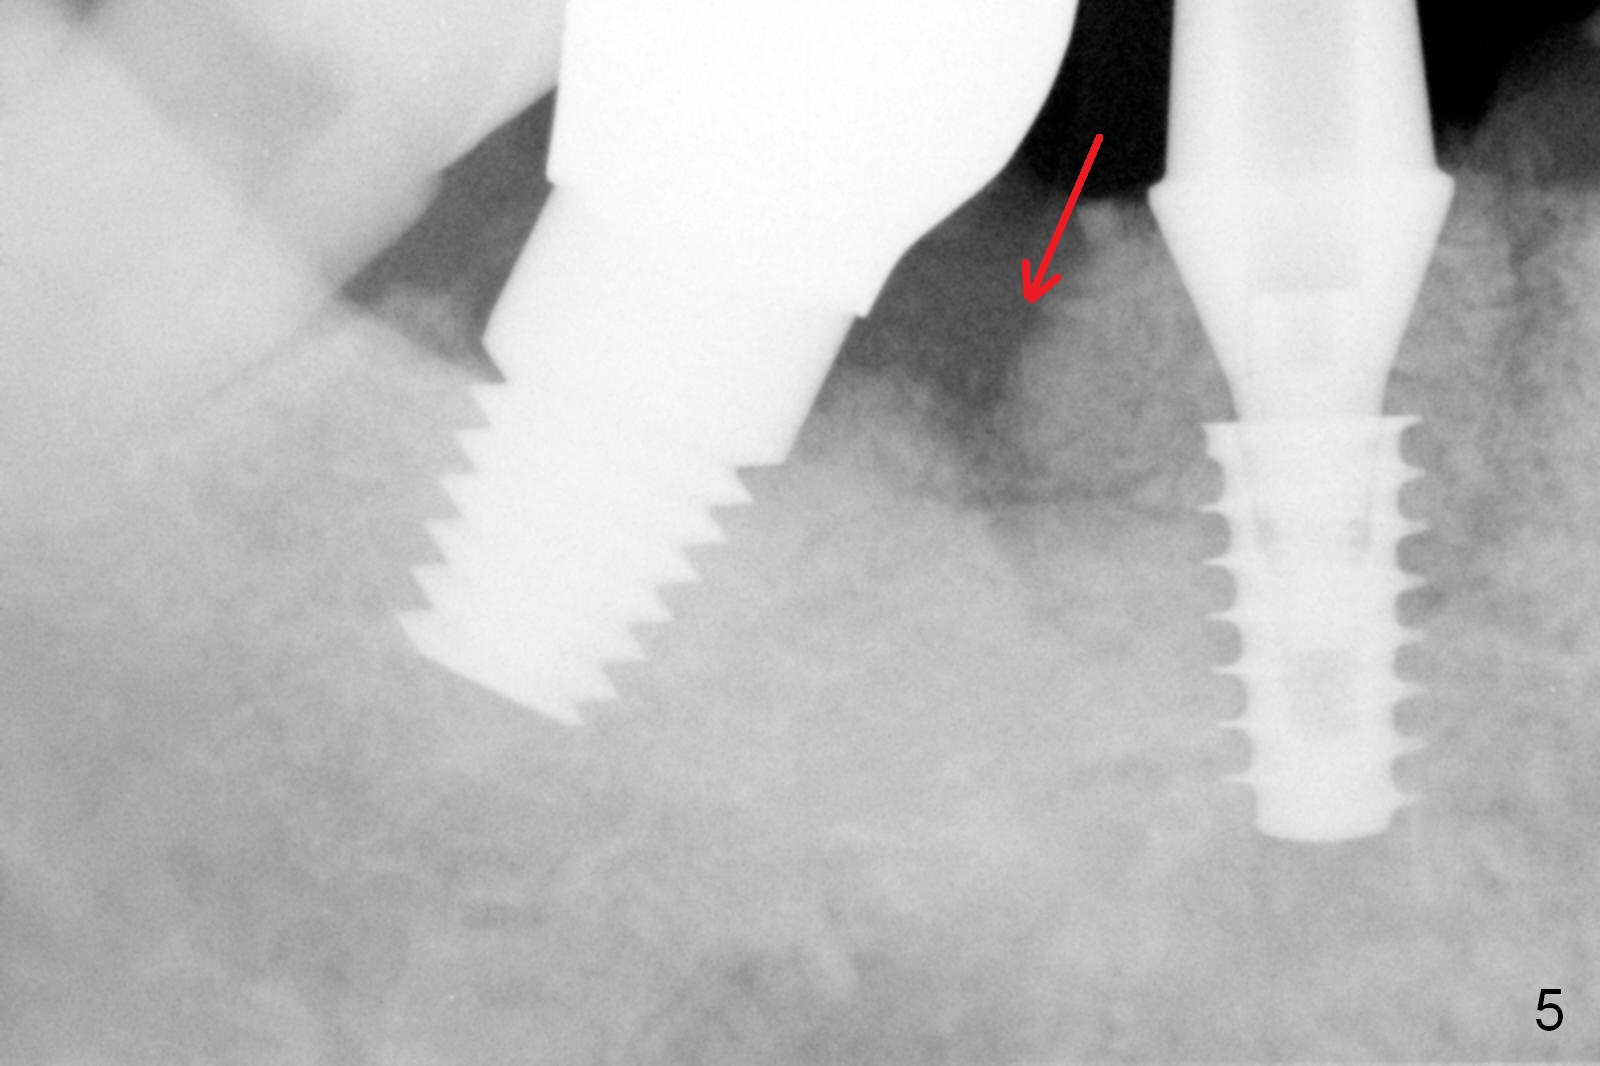

Extraction shows the large distal socket (Fig.1 D) and the thin and low septum (*) of the tooth #30. After Magic Split test confirms hard bone, osteotomy is initiated with 1.6 mm pilot drill with 11 mm stopper (Fig.2); there is 2.7 mm distance to the Inferior Alveolar Canal. Following Marking Bur, a 4.8 mm Magic Drill is used to finish the osteotomy with difficulty because of hard bone and ineffective local anesthesia due to infection. A 5x9 mm "dummy" implant is placed to determine the placement level relative to the distal crest (Fig.3 *). After removal of the dummy implant, an authentic one with the same dimension is placed with packing abundant allograft (.5-1.5 mm) and Osteogen (Fig.4 *); it appears that 4 to 5 threads (fins) of the implant (arrowheads) are engaged to the native bone for primary stability (>40 Ncm). Later more bone graft is placed distally (Fig.5 arrow). With the short implant placed not so deep, there is 6-7 mm clearance from the underlying canal (Fig.6). The patient is doing well 7 days postop (Fig.7). He feels that the provisional is too bulky buccally for the first 2 days postop. The buccal margin will be trimmed in another 2 weeks (dashed line). The patient in fact masticates on the right side postop. By the time he returns for provisional revision 1 months 10 days postop, he has mild pain. There is food entrapment. The provisional and the abutment are slightly loose, whereas the implant is stable with healing socket (Fig.8). A healing abutment is placed. The implant appears unstable nearly 5.5 months postop. The gap between the bone and implant seems to be large (Fig.9). The implant should have been larger and longer for fast healing. A healing screw is used instead. The site heals 10 months postop with an increase in bone density around the implant (Fig.10.) Prior to cementation of the final crown, the abutment is minimally exposed (Fig.11 (6.5x5.7(3) mm)). In fact the abutment screw becomes loose 2 months post cementation (1 year postop); it appears that crown/implant ratio is unfavorable (Fig.12). The implant is slightly placed mesially (cantilever). The patient cannot chew on the left. The tooth #19 is periodontally affected and the tooth #18 is missing. When bone loss is severe, the implant should be as large as possible and preferably tissue-level. The abutment screw is re-loosening 1.5 years post cementation (4 months post #19 socket preservation, Fig.13). The crown/implant ratio at #31 is more favorable than that at #30 (compare black lines). The crown at #31 has large contact area with the tissue-level implant (external), whereas the contact between the abutment and the bone-level implant is much less (internal). To prevent the abutment screw re-loosening (turning) in function, a screw driver (Fig.14 D) will be buried inside the crown/abutment after the screw is retightened. Make sure that the driver is in the middle of the access hole. Section the driver in situ obliquely (Fig.15); flat sectioning allows the driver to turn with the abutment screw in function. After insertion of plumber tape around the sectioned screw driver, use composite to fix the driver in place and seal the access hole (Fig.16). Occlusal check suggests weak link between the abutment and bone-level implant at #30.